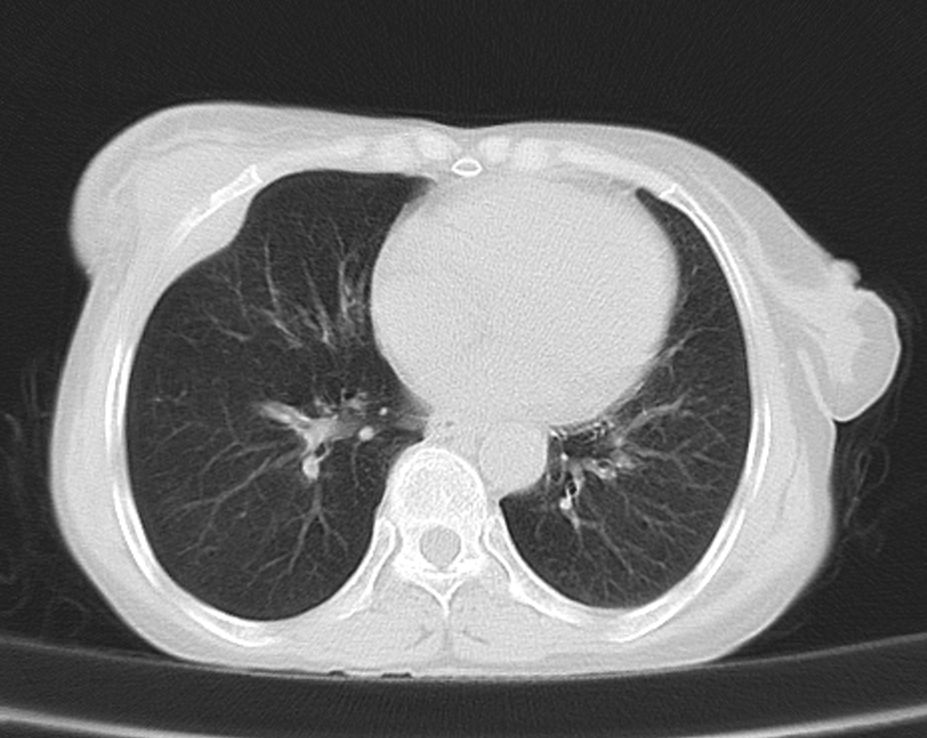

标题: CT21609:右乳包块1年,请各位讨论分析一下,乳腺CA, [打印本页]

标题: CT21609:右乳包块1年,请各位讨论分析一下,乳腺CA,

考虑---右乳癌并胸壁、肋骨、双肺转移。

考虑乳腺癌侵犯肋骨、胸壁及两肺转移可能性大。

右乳癌并胸壁、肋骨、双肺转移。

考虑右侧乳腺癌侵犯肋骨、胸壁及两肺转移。

支持考虑---右乳癌并胸壁、肋骨、双肺转移。

考虑右侧乳腺癌侵犯肋骨、胸壁及两肺转移可能。

考虑右侧乳癌并胸壁、肋骨及双肺多发性转移。